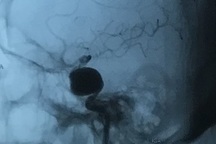

(Dân trí) - Đi khám vì mờ mắt, nữ bệnh nhân được bác sĩ chẩn đoán có khối phình động mạch khổng lồ, kích thước 6cm, trong khi bình thường chỉ 2-10mm.

PGS.TS Đồng Văn Hệ, Phó giám đốc Bệnh viện Hữu nghị Việt Đức, Giám đốc Trung tâm Phẫu thuật Thần kinh cho biết, hình ảnh khối to trong não bệnh nhân thực chất là khối phình mạch khổng lồ, kích thước hơn 6cm, trong khi bình thường 2-10mm. Tiên lượng đây là ca mổ phức tạp.

“Nhiều khả năng chúng tôi phải chia thành nhiều giai đoạn để mổ. Giai đoạn thứ nhất là tạo hình mạch máu mới, nuôi não bằng mạch khác, sau đó mới xử lý chỗ phình mạch vì liên quan quá nhiều cấu trúc”, PGS Hệ nói.